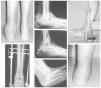

La reconstrucción del tobillo en la artropatía de Charcot, que con frecuencia se realiza tras un traumatismo, se indica ante la aparición de úlceras e inestabilidad. Una fijación rígida se obtiene mediante tornillos a compresión y en ocasiones con una placa condílea o un clavo intramedular retrógrado. Este último se emplea principalmente en casos de fractura luxación de tobillo o del retropié, aunque los autores prefieren los tornillos largos de 6,5 mm o tipo bolt porque proporciona un mejor control de la rotación y mantiene una mejor reducción (fig. 2).

Figura 2. A: visión posterior de un paciente de 46 años de edad con diabetes mellitus tipo 1 y un pie de Charcot. Presenta una importante deformidad y tumefacción a nivel del retropié. B: proyección radiológica lateral que muestra la luxación lateral del calcáneo bajo el peroné. La tibia se articula con el cuerpo y cuello del astrágalo parcialmente desintegrado, y se aprecia inestabilidad de la articulación de Chopart y colapso de la columna medial. C: se realizó un alargamiento del tendón de Aquiles y se utilizó un fijador externo híbrido para realizar distracción y conseguir la reducción del calcáneo bajo el astrágalo. Los pines se colocaron en la tibia proximal, la tuberosidad posterior del calcáneo y los huesos del tarso. D: una visión anteroposterior del tobillo confirma la reducción del calcáneo bajo el astrágalo y la desintegración del maléolo peroneal. E: proyección lateral en la que se observa la reducción del tobillo inestable y del retropié, con una doble fusión que se extiende a la articulación de Chopart, la columna medial y la articulación de Lisfranc. Se empleó aloinjerto de banco para rellenar los defectos. F: una proyección oblicua muestra la extensión de la fusión al tobillo previa osteotomía del peroné para acceder a dicha articulación. El alineamiento y la estabilidad mejoraron. G: visión posterior del pie y del tobillo tras la reconstrucción con un ligero valgo residual. El paciente está ahora andando con una plantilla doble (insert) y calzado con suela de balancín sin muletas, y se ha incorporado a su trabajo habitual como empleado de banca.